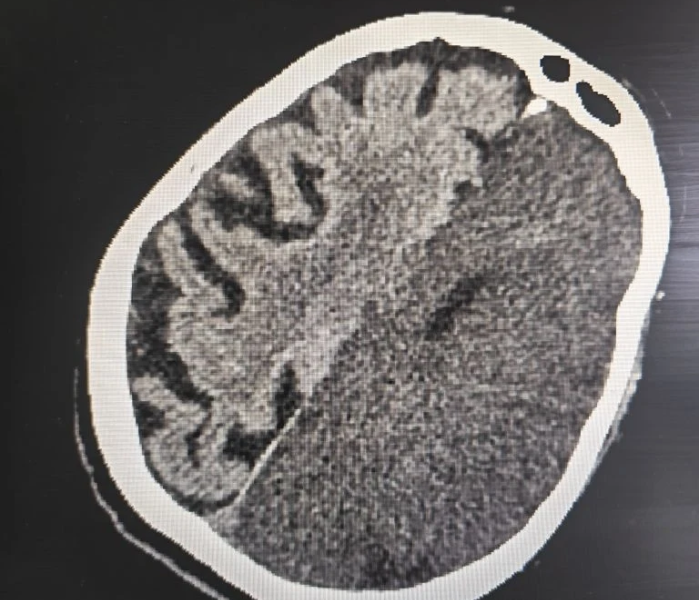

Мозг

Здоровье и спорт

10 апреля 2026

Пожилая пациентка с обширным инсультом и параличом пошла на поправку после лечения в воронежской БСМП №8